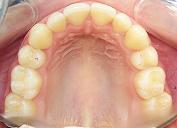

La inspección visual es uno de los pasos básicos en el diagnóstico. Se analizan primeramente parámetros extrabucales como son los tejidos blandos de la cara y articulaciones mandibulares. Seguidamente en el interior de la cavidad bucal, es necesario valorar el aspecto de los tejidos blandos, el estado de las encías y examinar diente por diente. Se prestará especial atención a la relación de contacto entre las dos arcadas dentales.

Dependiendo de cada paciente el diagnóstico necesitará una serie de pruebas y estudios complementarios, como pueden ser radiografías, fotos, o modelos de estudio montados en articulador ( este es un dispositivo que simula los movimientos mandibulares).